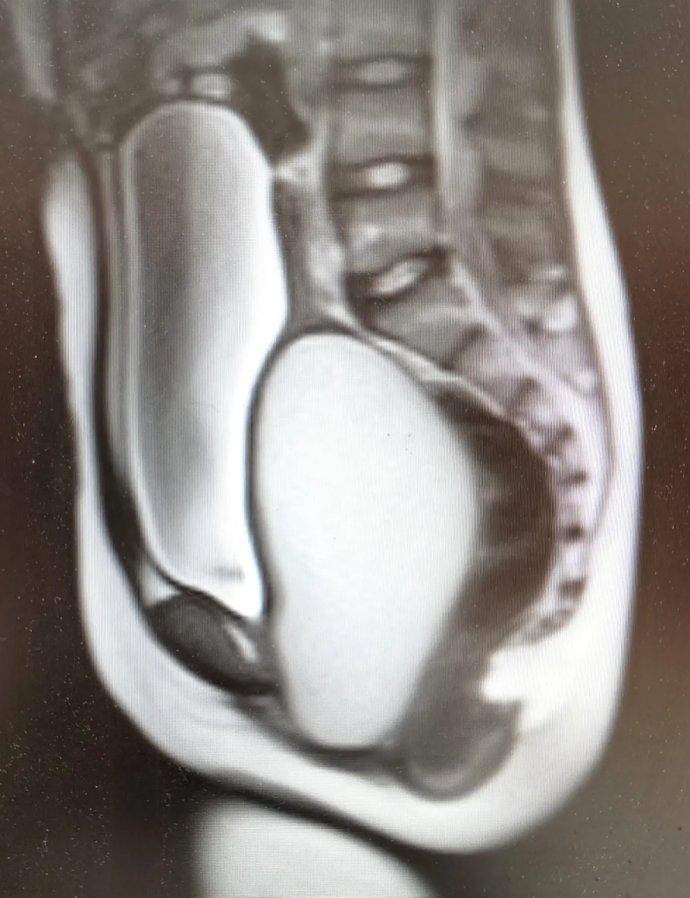

12歲花季少女出現周期性下腹痛,在其父母帶領下先后就診咸陽市兩家醫院,最終,她們選擇了延安大學咸陽醫院婦科。就診當日,趙倩蘭主管醫生詳細追問病史,患者自訴已間斷性下腹痛3月余,本次腹痛較前明顯加重,腹痛難忍。入院后醫生立即為其安排了婦科彩超及盆腔磁共振,發現該患者宮腔、宮頸及陰道上段充滿大量積血,積液壓迫膀胱及直腸,導致排便、排尿障礙。張素寧主任為其查體后發現,該患兒陰道竟無開口,導致經血無法排出,閉鎖處無隆起,無青紫,排除處女膜閉鎖,直腸檢查發現陰道上端有一包塊凸向直腸,包塊下緣距離肛門口約4-5cm,結合查體及相關輔助檢查,考慮該患者為陰道閉鎖,值得慶幸的是該患者其他系統暫未發現畸形。

盆腔磁共振圖像